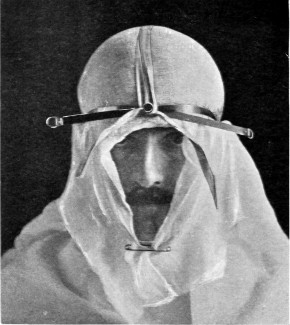

When the patient is fully under the anæsthetic, the final cleansing of the scalp is carried out and the operative field cut off from all possible sources of infection. In the States, in Cushing’s clinic, the anæsthetist is completely covered with a large sterilized sheet, which is fastened to the head of the patient. In this country we prefer that our anæsthetist should have full knowledge of the progress of the operation, and I think that the advantages are with us. In any case, the whole head is enveloped in gauze, two or three layers thick and about 18 inches square. This sheet is thrown over the patient’s head and maintained in position by means of the scalp-tourniquet (see pp. 14, 15). Around this sterilized towels are arranged, either fastened to one another or stitched to the scalp. When the operation is conducted in the temporal region the towels, unless fastened to the skin by means of a few sutures or safety-pins, tend to become displaced, and by so doing add to the risk of wound infection.

All surgeons must have appreciated the difficulty attendant on the application of forceps to, and the ligature of, divided scalp-vessels. The patient may lose a considerable quantity of blood, and much valuable time will be wasted before the more essential part of the operation is commenced. All this can, under ordinary circumstances, be avoided by the use of the scalp-tourniquet. As used by Cushing it consists of a rubber ring fashioned after the style of an Esmarch’s tourniquet, encircling the head and passing from the lower frontal region in front, above the ears, to the lower occipital region behind. A median tape, passing from glabella to occiput, prevents any tendency for the tourniquet to slip down over the eyes, at the same time acting as a convenient landmark for the superior longitudinal sinus.

The tourniquet, when applied with the correct pressure, should, under ordinary circumstances, completely control all hæmorrhage from the divided scalp-vessels. It should be noted, however, that[14] bleeding will be rather increased than otherwise if the tourniquet be so loosely applied as to impede the venous return without compressing the scalp arteries. A little experience will soon enable the operator to gauge the requisite pressure.

Fig. 4. The Scalp-tourniquet. Front View.

Fig. 5. The Scalp-tourniquet. Back View.

There is one other exception to the satisfactory working of the scalp-tourniquet. In the presence of a superficial cerebral tumour, especially when of a malignant nature, the normal communication between the intra- and extra-cranial vascular systems may be so exaggerated that those scalp-vessels which receive diploic and emissary venous communications will give rise to some trouble. This difficulty should be overcome—not by rapidity in the formation[15] and turning down of the flap—but by clipping each vessel as exposed or divided, by the application of pressure and by foraminal occlusion (see also p. 17).

I found Cushing’s tourniquet rather inconvenient in its application, and, after various modifications, am accustomed to use the one depicted in the illustration. It consists of two flat metal bands connected posteriorly by a strong rubber connecting link, the two bands passing in front through a metal fixation piece possessing a screw which, when tightened up, allows of the maintenance of the desired pressure. The median tape, previously mentioned, helps to keep the tourniquet in position.

The tourniquet is applied as follows: the whole head is enveloped in gauze—two or three layers thick, and cut to the size and shape of a large handkerchief. The tourniquet is slipped over the head,[16] as low down as possible, and then tightened up. The median tape, having a loop behind through which the tourniquet passes, is laid in the middle line and tied round the screw on the fixation piece.

The gauze should then be moistened with saline solution or some mild antiseptic, so that it clings tightly to the underlying scalp and becomes sufficiently translucent to allow of the recognition of any underlying landmarks that may have been previously mapped out with the scalpel, iodine, silver nitrate, or aniline pencil.

The scalp-flap is then framed by incisions carried down to the bone, through gauze and scalp, in one sweep. The flap is turned down and covered with gauze. By the adoption of this method hæmorrhage from scalp-vessels is efficiently controlled and the risk of wound infection is reduced to a minimum.